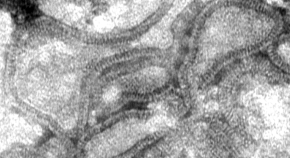

Andrea Superti-Furga, Ron Wevers, Clara van Karnebeek, Luisa Bonafé and colleagues identify mutations in NANS, which encodes the sialic acid synthase, in nine individuals with severe infantile-onset developmental delay and skeletal dysplasia. They describe abnormal metabolites accumulating because of deficient NANS enzyme activity and show that impaired sialic acid synthesis in zebrafish perturbs skeletal development, which can partially be rescued by supplementation with exogenous sialic acid.